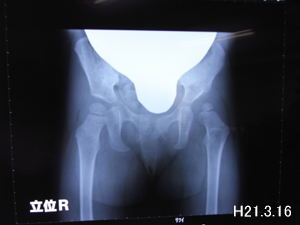

今回も立位のレントゲンと触診がありました。

レントゲンを見てもわかるように脱臼していた方は骨と骨の間が空いています

(骨頭壊死はしてないそうです!良かった!)

これは歩き出してからの治療開始の子にはしょうがない事と言われました

これからの臼蓋の角度や骨頭の成長を見守るだけのようです